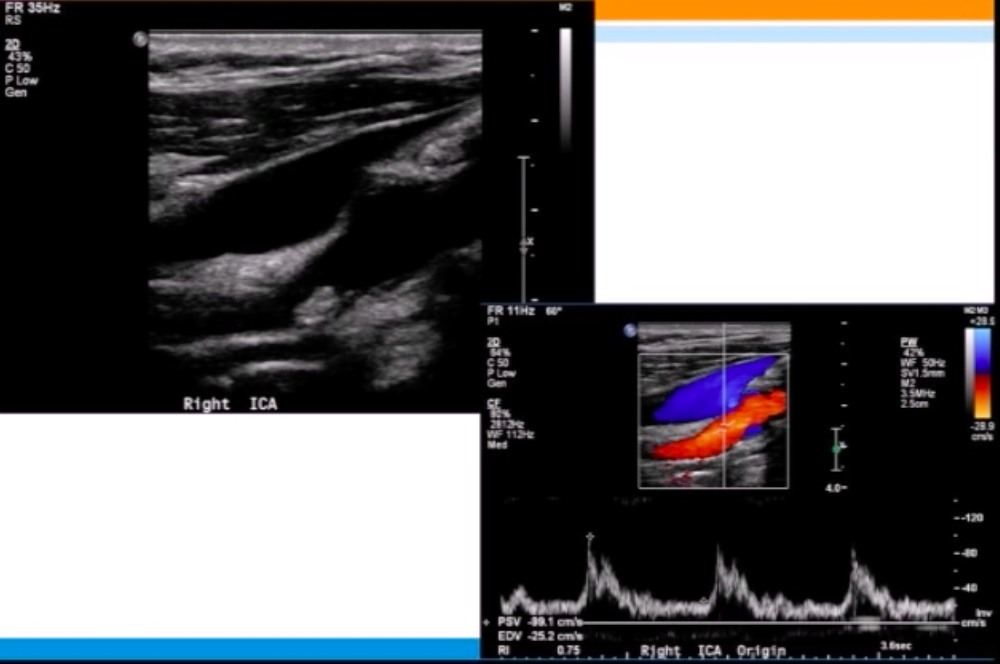

Patient has Lt ICA 100% occlusion. Rt carotid system shown below. PSV = 208 cm/s in proximal Rt ICA.

Most likely diagnosis?

mild Rt ICA stenosis (<50%)

since Lt ICA is 100% occluded, there should be elevated Rt CCA velocities (CCFA*)

plaque in proximal Rt ICA is <<50% ⇒ elevated velocities across Rt ICA are likely due to CCFA

*CCFA = compensatory carotid flow augmentation